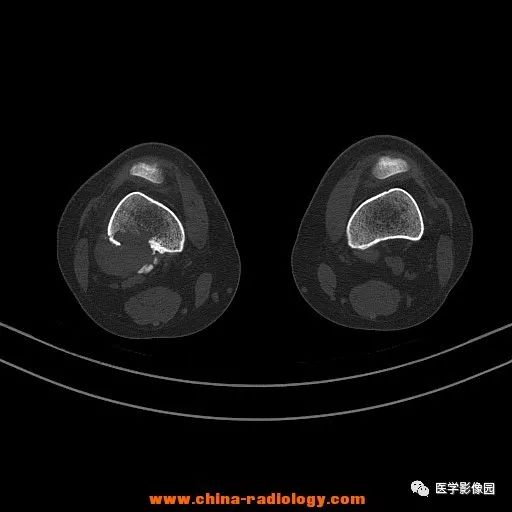

患者女性,29岁,右膝关节痛疼3月余,局部无红肿。

影像学表现:右股骨远端外后方可见局限性骨质破坏及软组织肿块,边界清楚。

病理结果:梭形细胞瘤